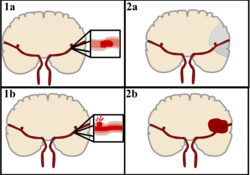

Classification

There are two main categories of stroke. Ischemic (top), typically caused by a blood clot in an artery (1a) resulting in brain death to the affected area (2a). Hemorrhagic (bottom), caused by blood leaking into or around the brain from a ruptured blood vessel (1b) allowing blood to pool in the affected area (2b) thus increasing the pressure on the brain.

Stroke can be classified into two major categories: ischemic and hemorrhagic.[19] Ischemic stroke is caused by interruption of the blood supply to the brain, while hemorrhagic stroke results from the rupture of a blood vessel or an abnormal vascular structure. About 87% of stroke is ischemic, with the rest being hemorrhagic. Bleeding can develop inside areas of ischemia, a condition known as "hemorrhagic transformation." It is unknown how many cases of hemorrhagic stroke actually start as ischemic stroke.[2]